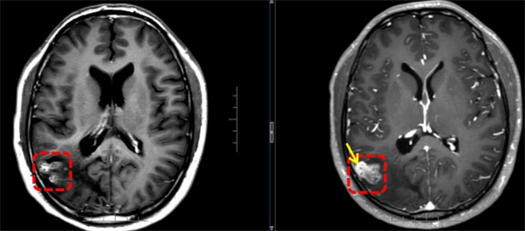

接诊的该院神经外八科二区副主任陈俊喜和王艮波主治医师,对比李正历次头部影像,发现病灶不仅位置移动,还呈现“隧道征”,高度指向脑裂头蚴病。后续血清检查结果也提示裂头蚴抗体阳性。

黄色箭头:虫体最新移动所在位置

“除近期的癫痫大发作,患者此前频繁出现视野闪光、画面感,其实也是癫痫发作。”陈俊喜解释,从影像来看,虫体已从大脑深部爬至表层,正是手术取出的好时机。于是,他带领团队快速安排了裂头蚴捉取手术,成功从李正脑内取出一条长约18cm的活虫。